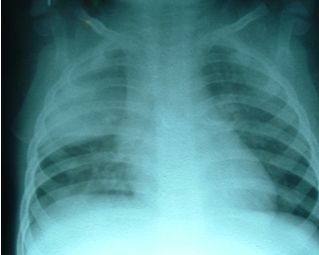

La neumonía alveolar (también denominada lobar, lobular o neumonía segmentaria) es en general causada por patógenos bacterianos, y Streptococcus pneumoniae en particular, sobre todo cuando se acompaña de recuento elevado de leucocitos periféricos, las concentraciones de proteína C reactiva (PCR) y fiebre alta, lo que justifica el tratamiento con antibióticos.

Para aumentar la probabilidad diagnostica de neumonía bacteriana, y minimizar la variabilidad entre los pacientes, se utilizaron criterios de selección predefinidos, que incluían radiografía de tórax, la temperatura corporal y hallazgos de laboratorio.